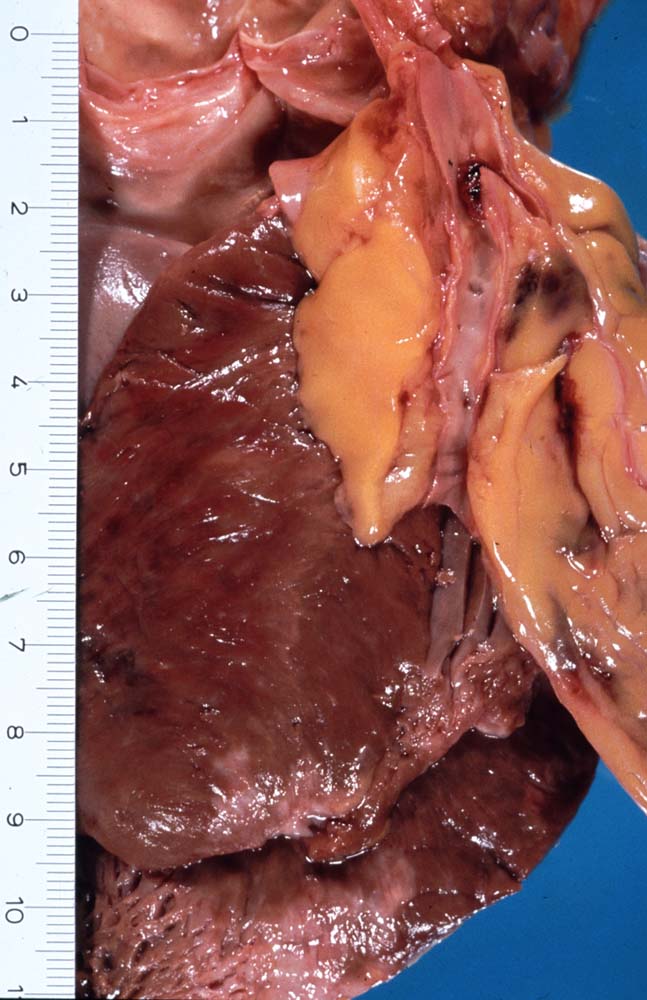

Makroskopisch sind Thromben am besten auf Querschnitten in 3 bis 5mm Abständen durch die Koronargefässe darstellbar. Thromben, die zum Tod des Patienten geführt haben, erkennt man meist makroskopisch. Mikroskopisch findet sich ein Kontinuitätsunterbruch in einer entzündlich veränderten fibrösen Deckplatte über einem Atherom. Dadurch gerät der lipidreiche Kern des Atheroms in Kontakt mit dem luminalen Blutstrom und dies führt zur Ausbildung eines Plättchen-Fibrin Thrombus und zur Einblutung in das Atherom. Meist zeigt der Thrombus Zeichen der beginnenden Organisation. Histologisch ist bei einer Ruptur die denudierte Endotheloberfläche von einem luminalen Thrombus bedeckt.

Makroskopie

Befund

Pathologischer Befund

Normalbefund